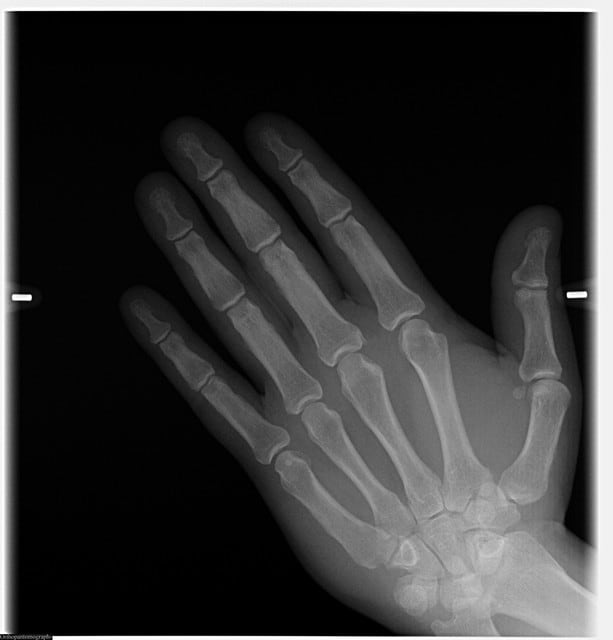

la qualité te plait cyber?:)

il y a un panel de taille et de morphologie de patient et les réglages restent top

Les radios sont extraordinaires !!!! Quel beau jouet ,ça fait envie.

D'accord avec Marc: la pano est magnifique !